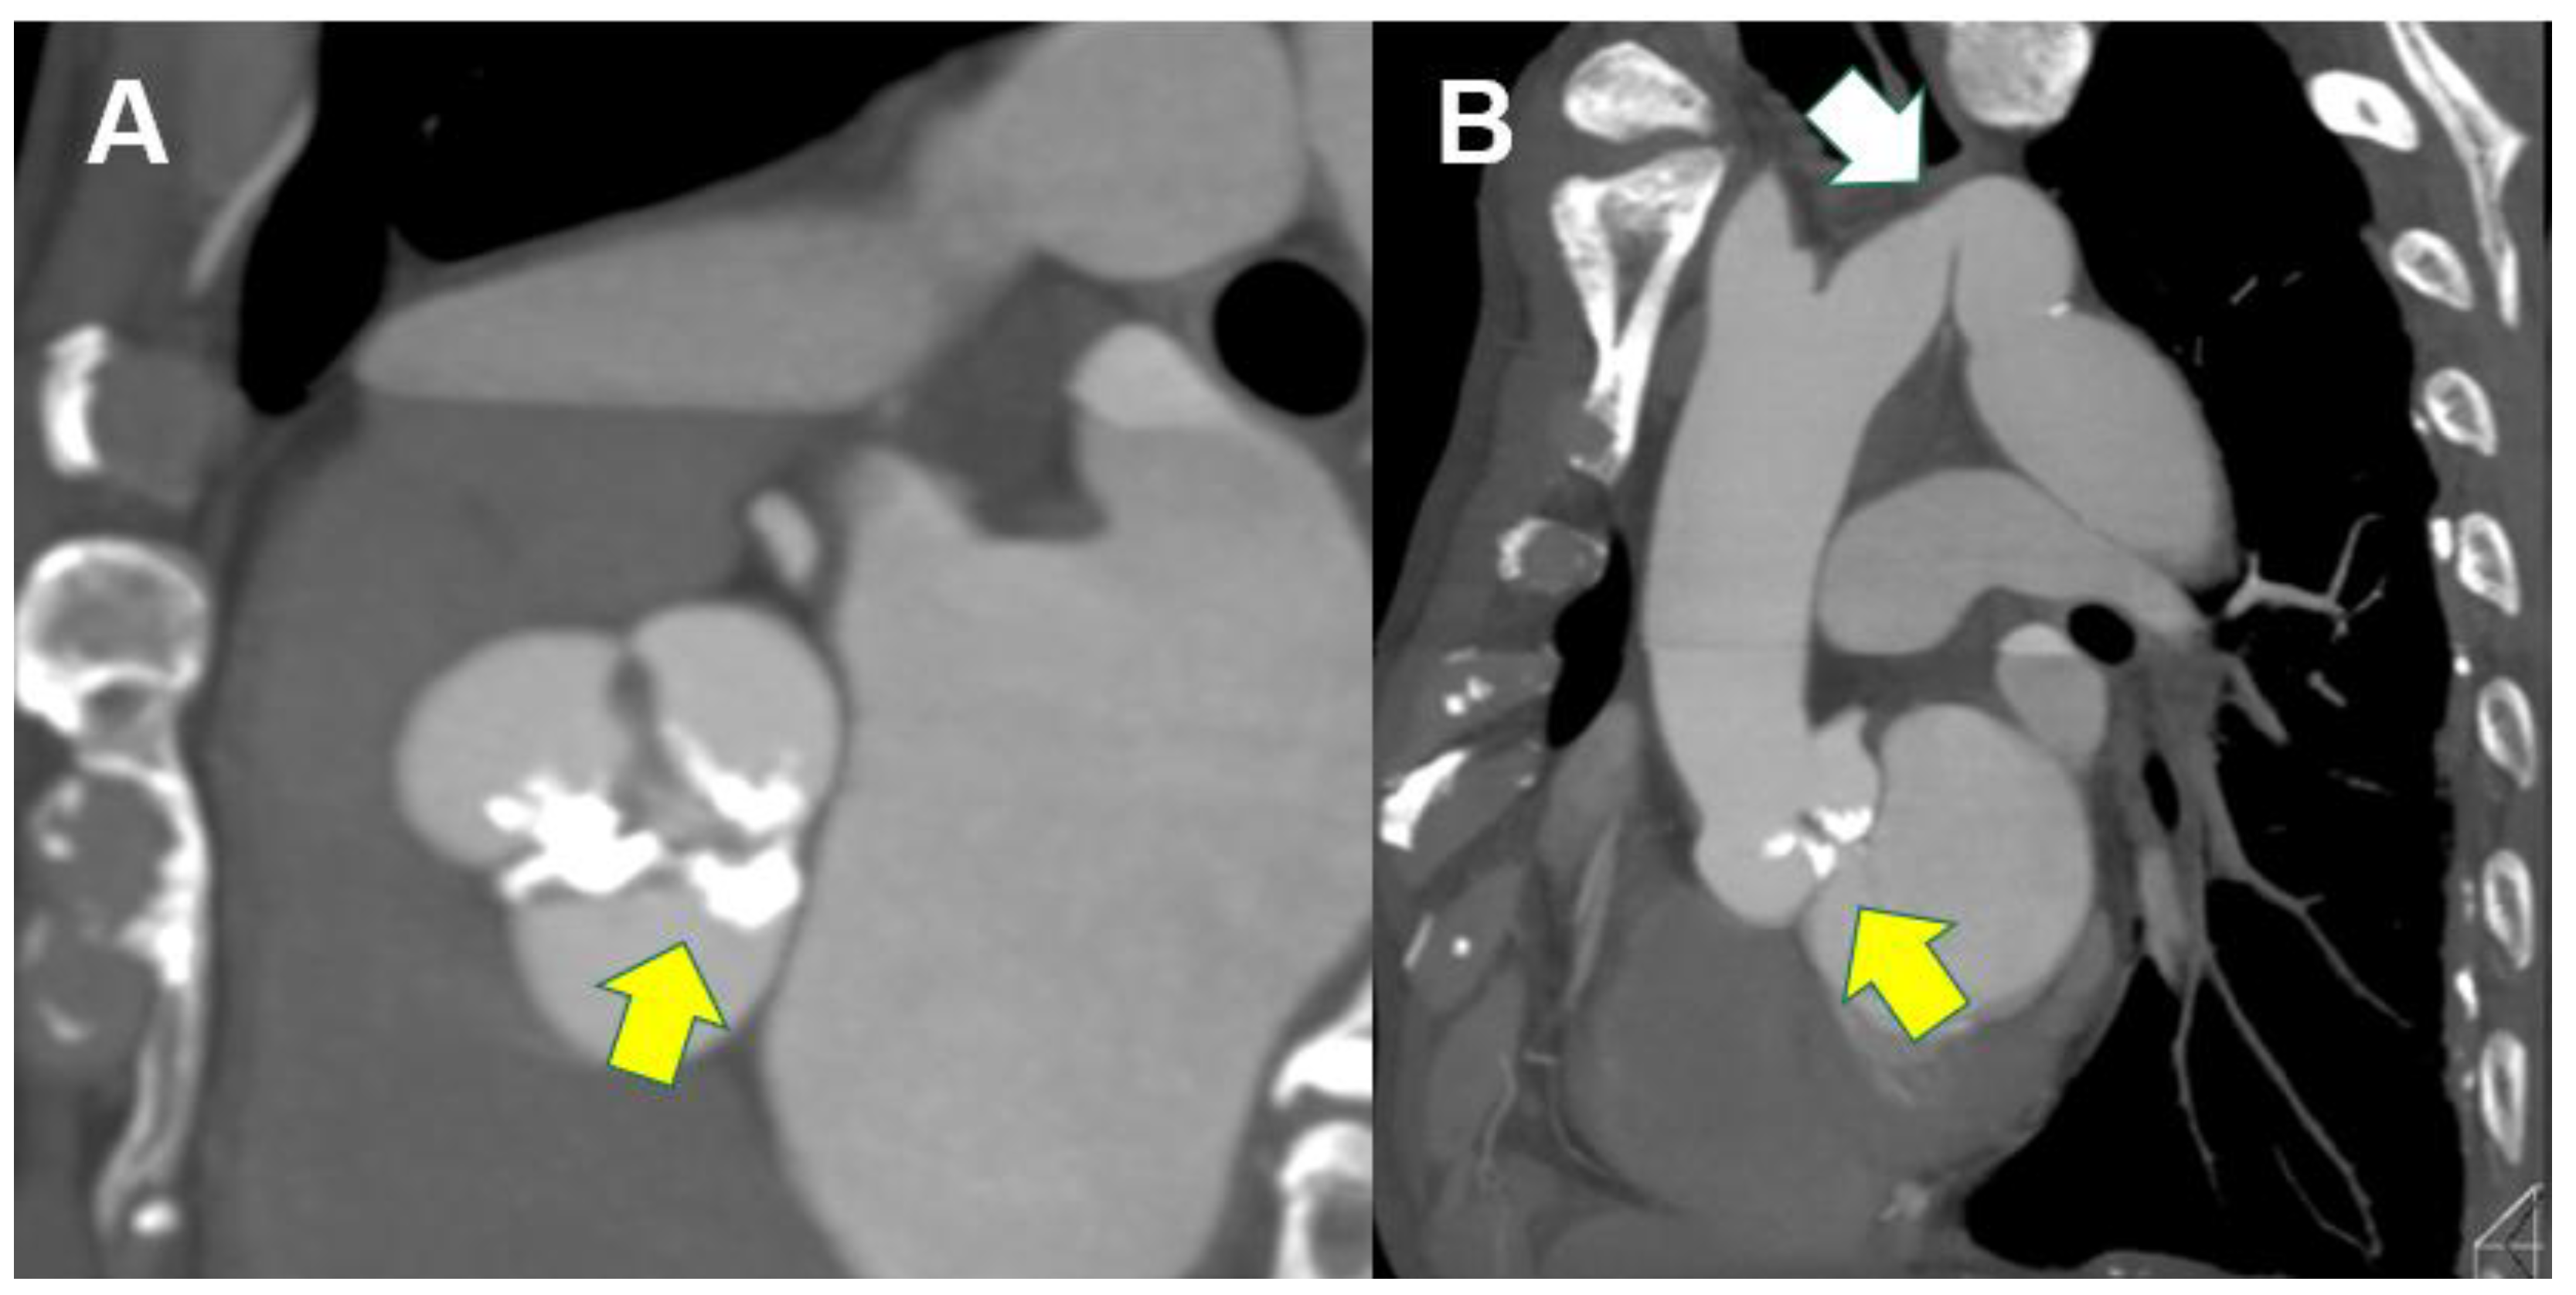

4.4. CT Analysis Before Valve-In Valve TAVI or TAV in TAV